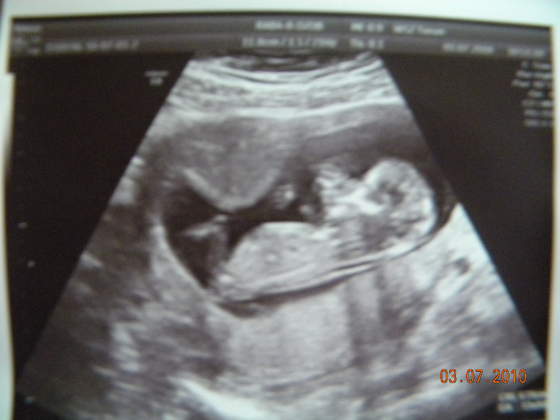

więc wizyta bardzo pomyślna jestem zadowolona, przezierność karkowa w normie, ładna kość nosowa i żuchwa etc niestety jeszcze nie wiemy co mieszka w moim brzuszku

ale pan doktor pochwalił fasolkę bo ładnie dała się pomierzyć

) no i dziś już miałam robione po raz pierwszy usg przez powłoki brzuszne